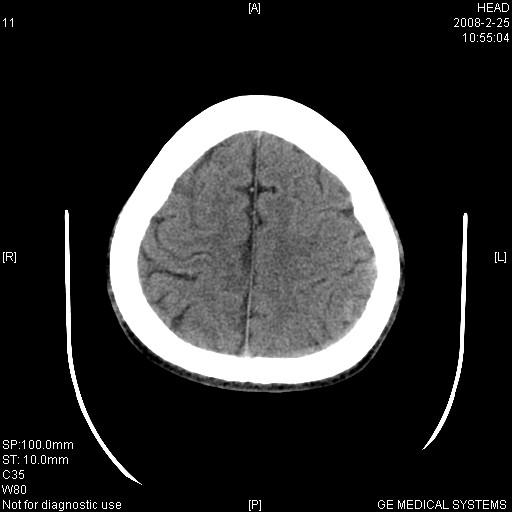

男,23岁,下颌部外伤一天,主因头痛、头晕、左面部麻木来院。两年前有外伤史,至左眼视力差。余无异常。骨窗未见异常故未上传。

强化检查明确诊断,左侧顶叶可见钙化改变。

有外伤,支持左侧海绵窦血管瘤。左顶后叶高密度影,伪影待排。